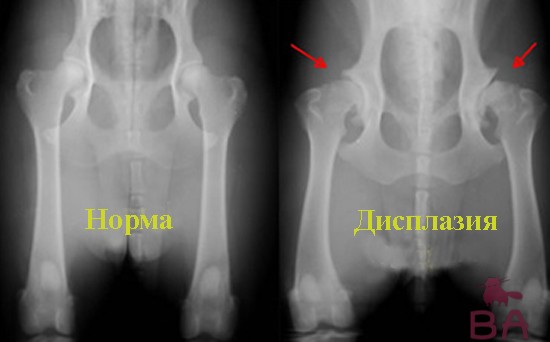

Если есть подозрение на то, что по генетическим нарушениям выявляется дисплазия, то в таком случае лучше пойти сделать рентген суставов, в таком случае легче будет увидеть есть ли эта болезнь у собаки или нет.

Дисплазией является такая болезнь, которая способна вызвать деформацию и разрушение суставов, а потом уже и аппарата опорно-двигательной системы. Неправильное формирование суставов или повреждения в виде трав, когда зазоры между впадинами в костной системе достаточно велики, то в таком состоянии образуется трение ткани хрящей, тем самым способствуя вызывать сильные боли.